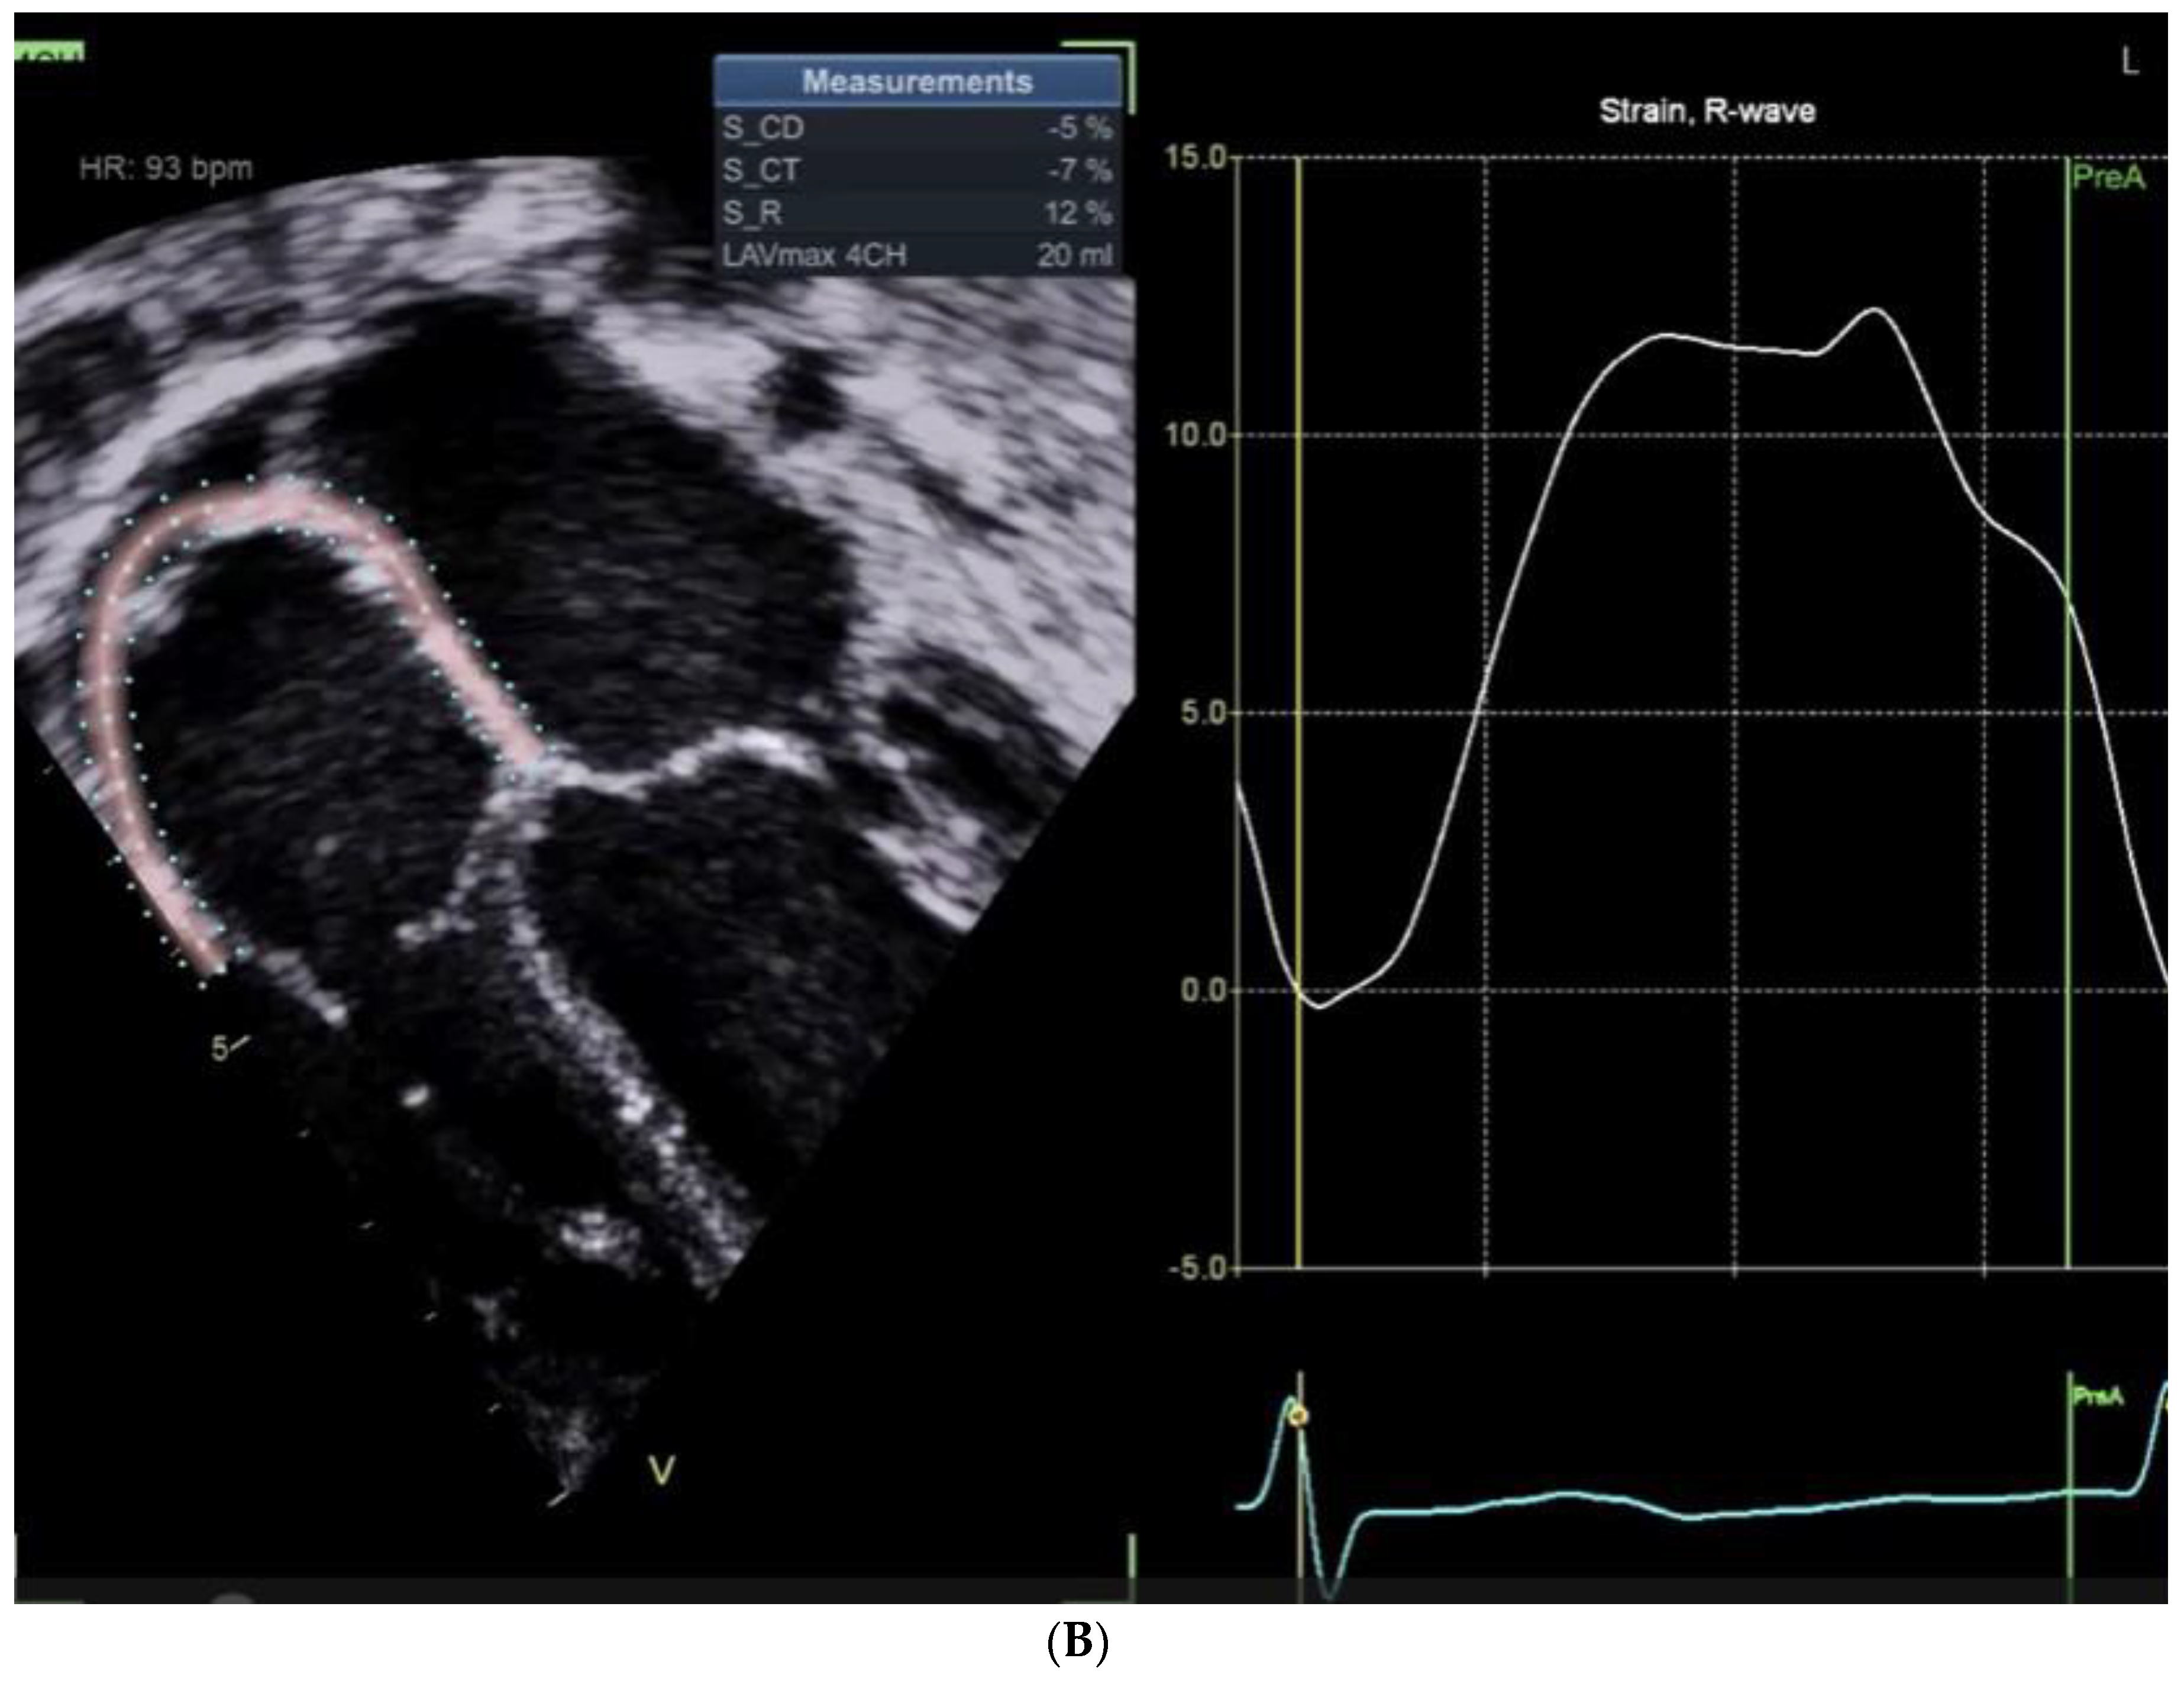

Right Atrial Functions Are Shown in Figure 1A and Figure 1B.

Table 1 Summarizes the Findings of Figure 1 A and B

Despite successful surgical results and myocardial functions, the Right Atrial (RA) conduit function is noticeably reduced, reflecting the lack of passive atrial shortening, and the reservoir function is mildly reduced. Notably, the impaired passive shortening is compensated by an exaggerated atrial kick compared to the patient who has not undergone ASD closure.

Figure 1. A: Right atrial functions assessment in a patient following a non-ASD cardiac surgery (mitral cleft closure). B: Right atrial functions assessment four days following post-ASD closure, presenting a small rim of pericardial effusion developing in the vicinity of the right atrium.

S/P ASD Closure S/P Mitral valve repair Cut-offs

(Absolute values)

Conduit -5 -14 >11%

Reservoir 12 16 >18-22%

Contractile -7 -2 >8-12%